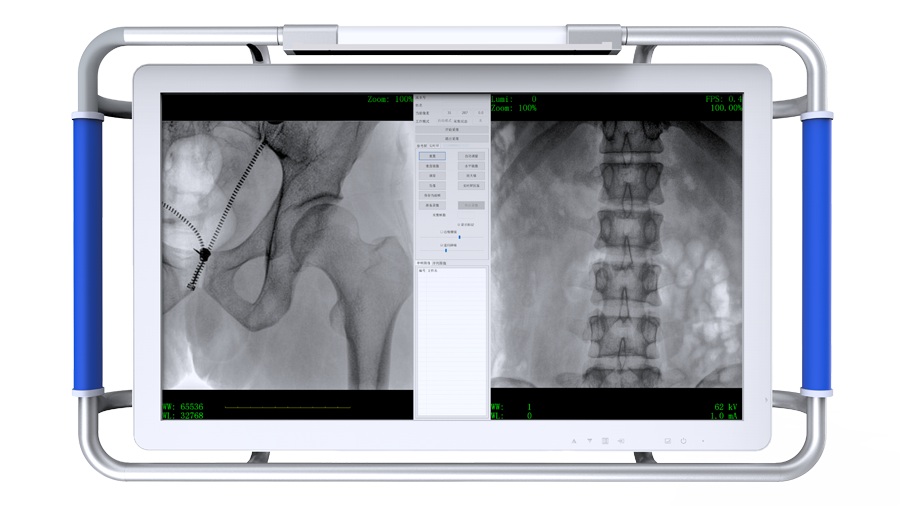

大視野 小身材 PLX C211

臨床應(yīng)用廣泛,適用于關(guān)節(jié)手術(shù)、創(chuàng)傷手術(shù)、脊柱手術(shù)、疼痛治療等。

●設(shè)備搭配觸控屏,指尖輕觸即可完成多種操作。

●屏幕內(nèi)置DICOM醫(yī)學(xué)曲線,幫助辨認(rèn)細(xì)微組織的密度變化。

●27英寸大尺寸顯示器,更大視野,方便觀察微小結(jié)構(gòu)。

●一屏雙顯,可同時觀察正側(cè)位圖像,便于對比觀察。